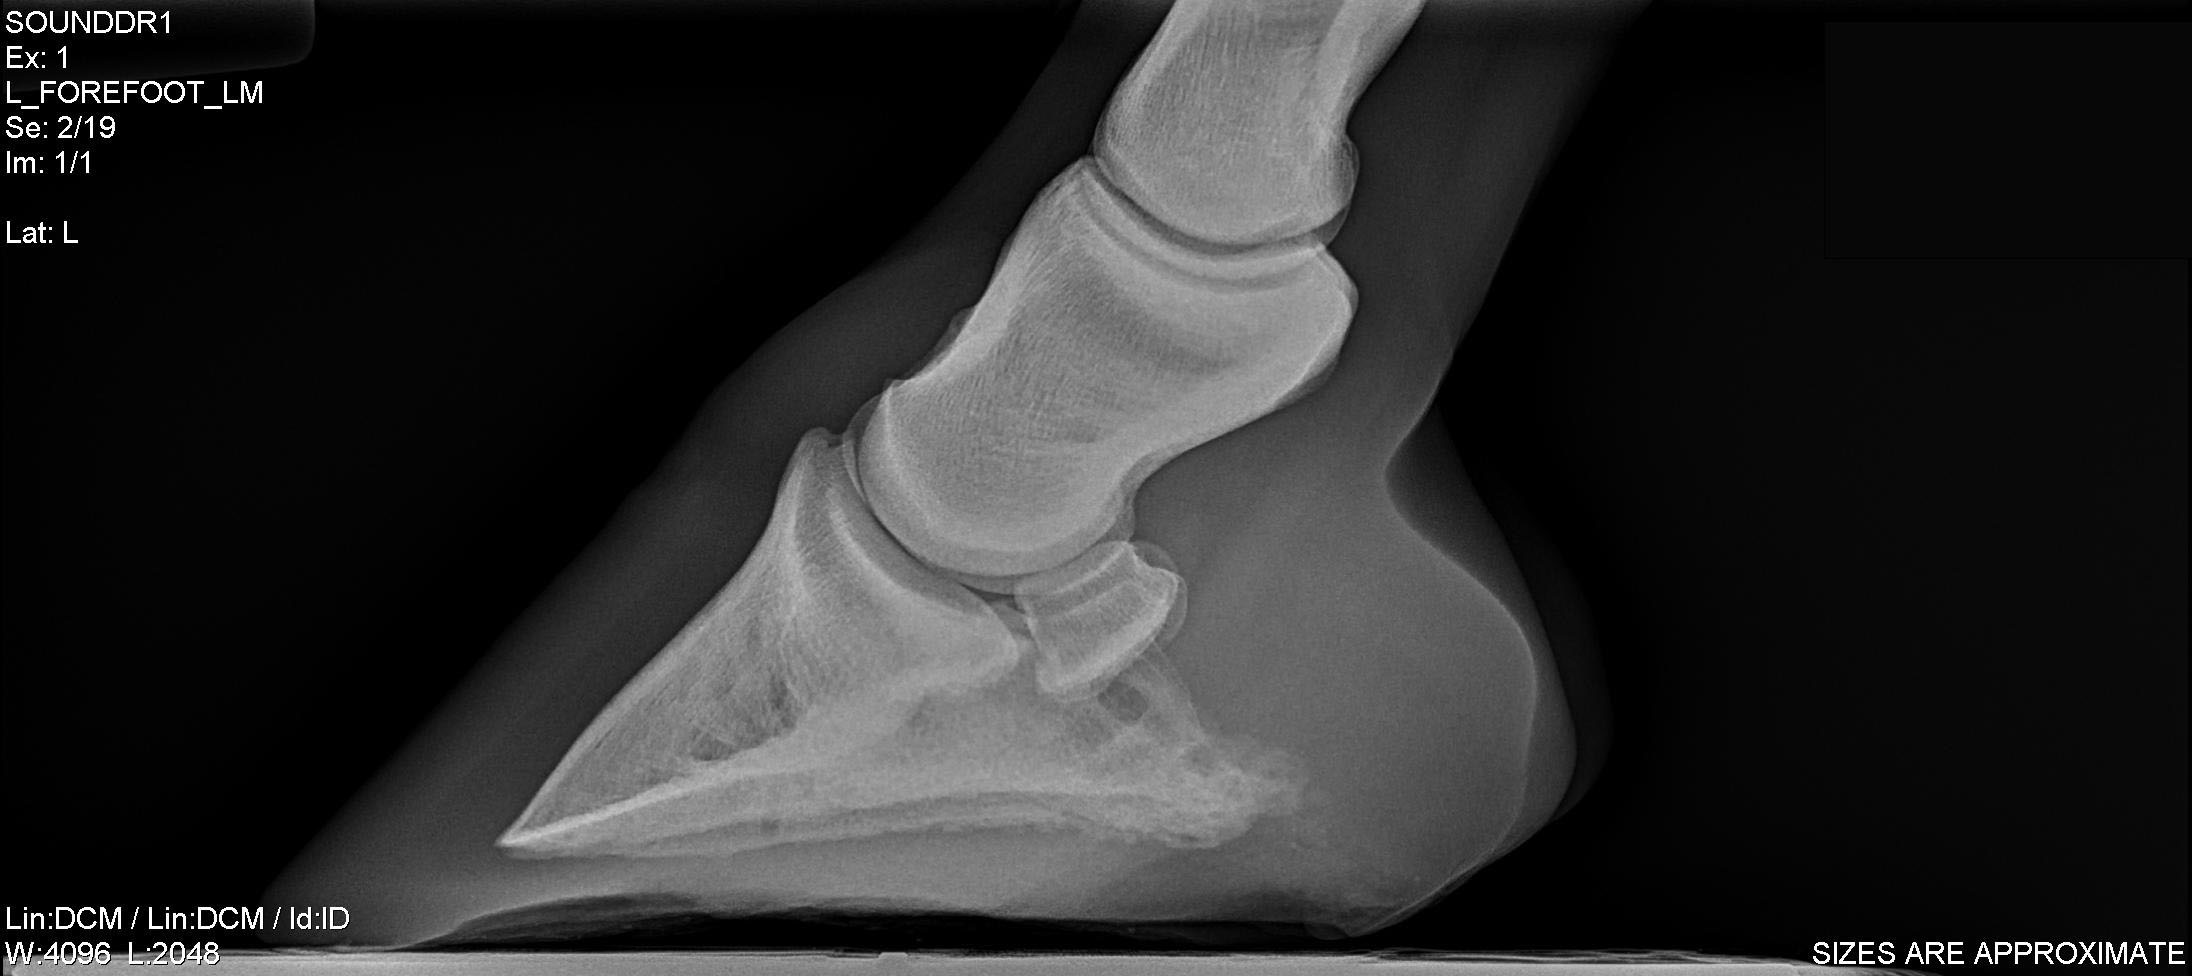

Equine Foot Radiographs Views . much has been written about specific views for imaging the equine foot. the following radiographs are the lateral, dorsopalmar, sixty degree dorsoplamar (60 dp) and sixty degree dorsopalmar. Almost without exception, the primary. radiographic examination of the equine foot can provide the veterinarian and farrier with a wealth of. indications to radiographic the foot include lameness that localized to the region, farriery, regions wounds/lacerations,. there are two main views that are most helpful to the hoof care provider: current radiographic techniques applied to the equine foot allow more accurate diagnoses and reduce radiation exposure.